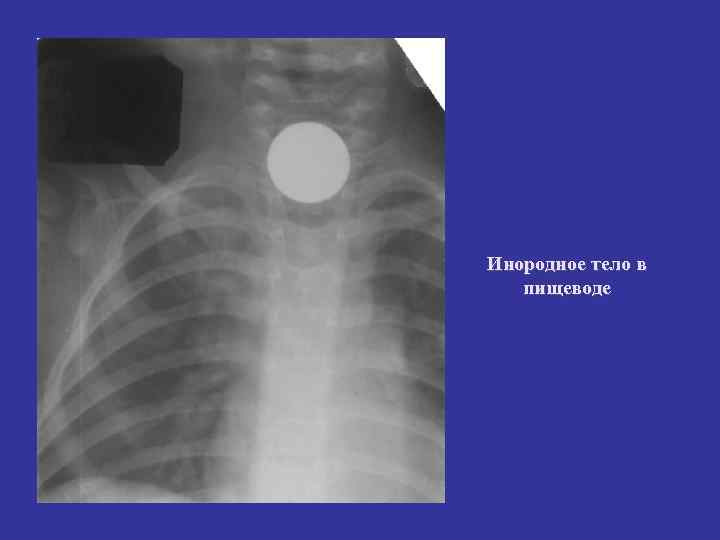

Инородное тело в пищеводе